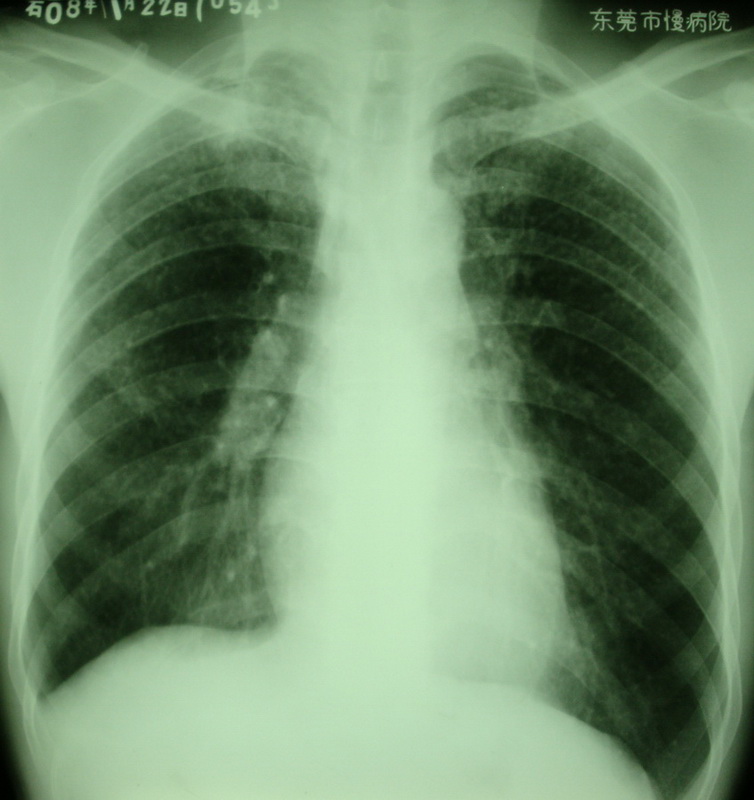

按顺序依次是:(都有粉尘职业史)

周某,男,40岁,i尘肺。